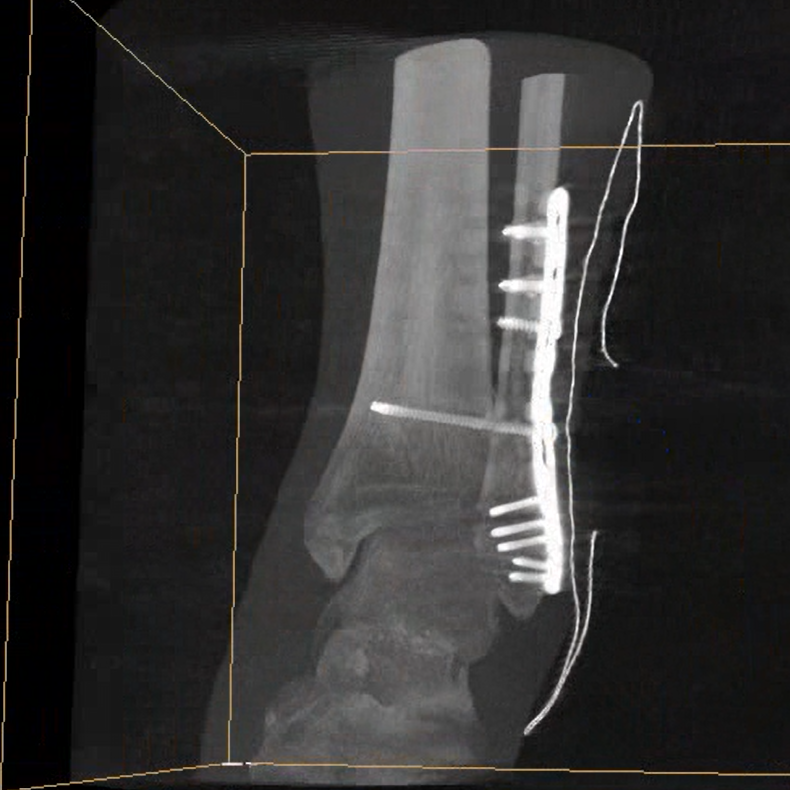

術(shù)中三維成像和橫斷面圖像提供多角度的手術(shù)診斷信息,輔助醫(yī)生進行術(shù)中評估判斷,諸如骨折復(fù)位情況和內(nèi)植入螺釘?shù)某叽绾臀恢?,輔助手術(shù)更好地完成。

平板垂直升降運動 便于術(shù)中微調(diào)平板與拍攝主體的距離,更加貼近病灶體,成像范圍更大,圖像更清晰。